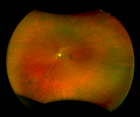

MonacoPro provides an exciting new way to enhance your clinical exam. The only ultra-widefield retinal imaging device with integrated Spectral Domain OCT, MonacoPro produces a 200° single shot optomap image in less than ½ second and also provides cross-sectional 40° OCT views of retinal structures. Engineered for efficiency, MonacoPro captures up to five imaging modalities for both eyes in just 90 seconds, optimising workflow, streamlining diagnostics, and delivering superior patient care.

optomap Image Modalities

- colour rg

- Sensory Retina

- Choroidal

- green af

- SD-OCT

- 3-in-1 Color DepthTM Imaging provides important clinical data from the retinal surface, through the choroid